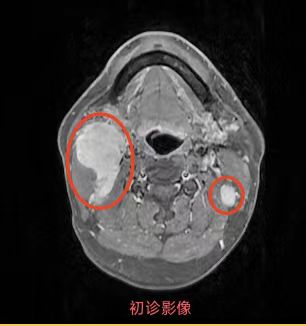

同步放化療(鼻咽癌伴頸部淋巴結轉移)